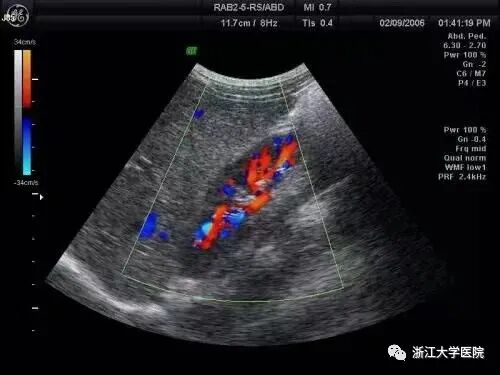

B超对实质性器官(肝、胰、脾、肾等)以外的脏器,还能结合多普勒技术监测血液流量、方向,从而辨别脏器的受损性质与程度。例如医生通过心脏彩超,可直观地看到心脏内的各种结构及是否有异常。

彩超检查,是指“彩色多普勒诊断”。 它是利用现代科技将多普勒信号转变为彩色信号,并与二维黑白声像图叠加,实现彩色血流显像,使得体外观察和评价血管内空间及血流状态成为可能。可见彩超主要用于心脏病检查和人体各脏器内外的主要血管的血流检测。如在诊断消化、泌尿系统疾病中,通过彩超获取门静脉、肝动脉、肾动脉的血流信息。  如果病变尚未果及上述血管,而仅为胆系、胰腺疾病,则大可不必做彩超,以免加重经济负担。